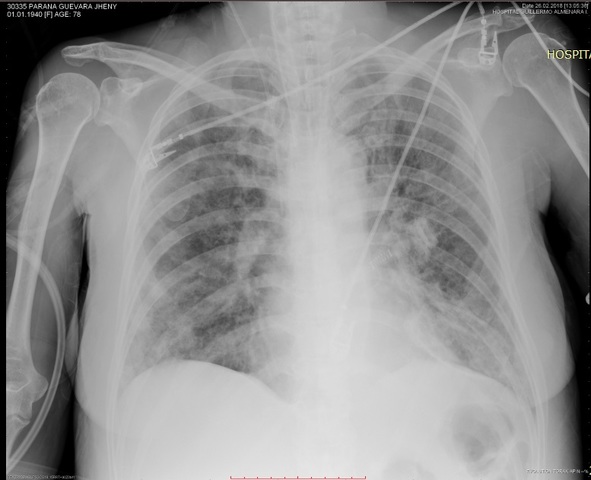

SE RECIBE RESULTADO CULTIVO SECRECIÓN BRONQUIAL (03-03-2018): AISLÓ KLEBSIELLA

I/C INFECTOLOGIA

SE TOMAN MEDIDAS DE AISLAMIENTO

ACTUALIZA ANALITICA, RX TORAX